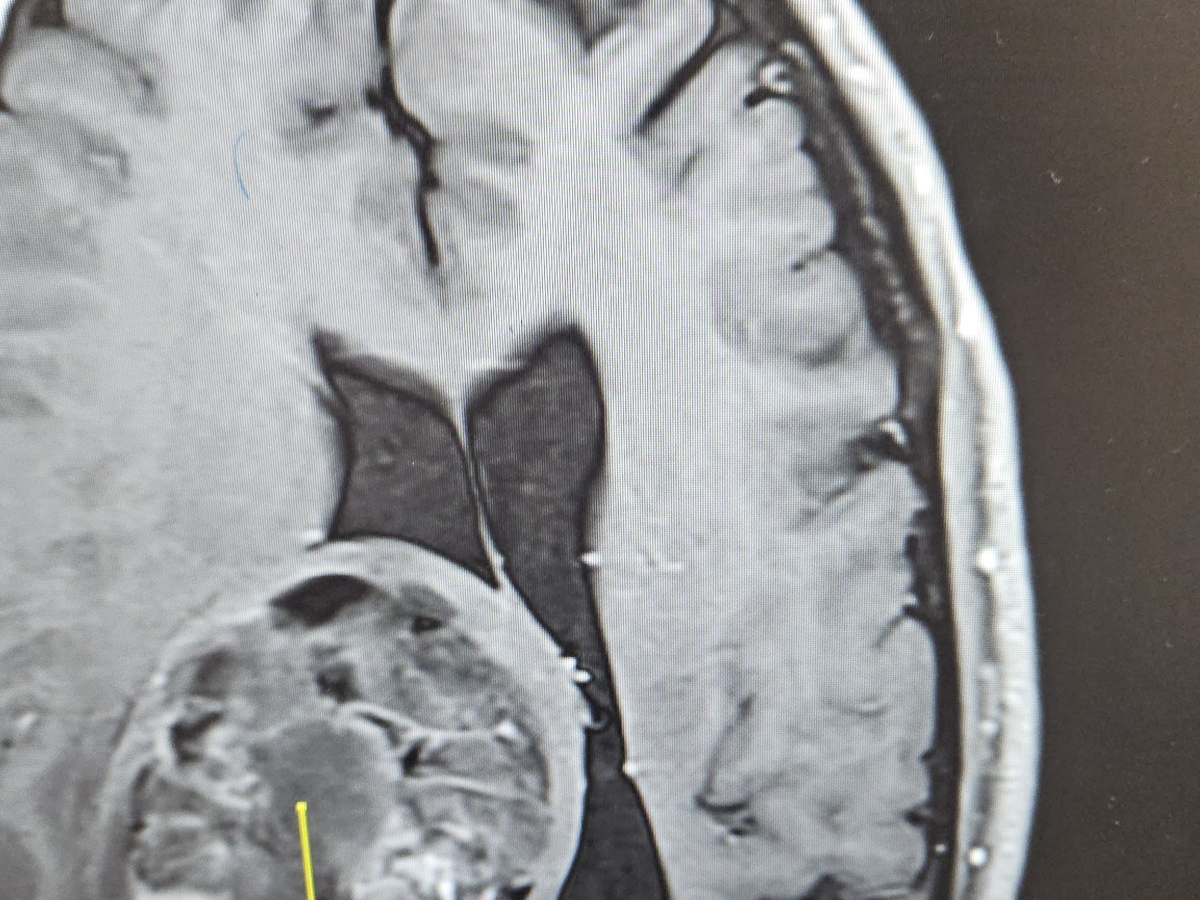

In November of 2024, I was diagnosed with a rare brain tumor called an Oligodendroglioma. Since that time, I have had two Craniotomies to remove approximately 90 percent of the tumor. The remaining tumor had crossed the midline of my brain and could not be removed. I have since undergone 30 sessions of radiation and I am now undergoing 12 months of chemotherapy.

I have had to stop working as the tumor damaged portions of my optic nerve and as a result I have left homonymous hemianopia, which is a vision deficit on the left side of both eyes. Thankfully my central vision was spared.